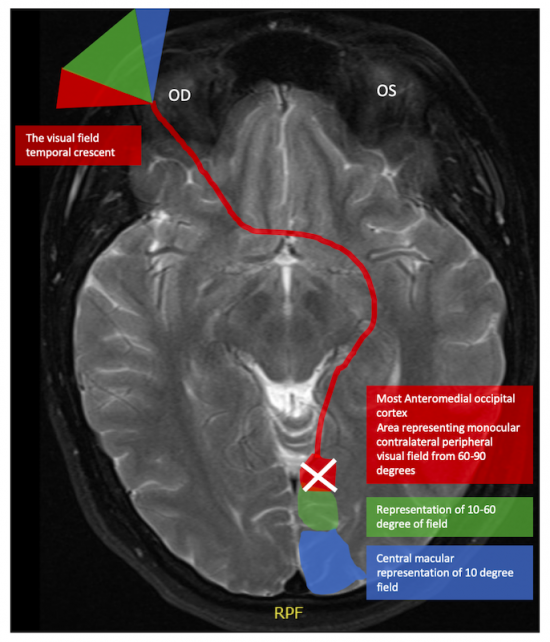

The etiology for this special monocular visual field defect is due to the distribution and overlap of the nasal and temporal visual fields. The normal visual field in degrees from the central point is 60 degrees nasal, 50 degrees superiorly, and 90-100 degrees temporally (Figure 1). The nasal and temporal hemifields in each eye overlap but the monocular temporal crescent has no perimetric correlate in the fellow eye because the temporal visual field is larger than the nasal visual field, hence there are more crossing nasal fibers than there are ipsilateral temporal fibers with a 53:47 ratio. [2] The extra nasal fibers that cross accounts for the non-overlapping contralateral temporal crescent. These fibers end up in the most anterior medial striate cortex and compromise 8-10% of the striate cortex. [3] This monocular representation in a retrochiasmal pathology is attributed to the monocular innervation in that area.[4] Thus, 30-40 degrees of the peripheral temporal visual field is unpaired and has unilateral representation in the contralateral visual cortex. Damage to this area of the visual cortex leads to the contralateral temporal crescent (Figure 2.)[5][6]

Patients with an acute onset of the temporal crescent syndrome should undergo neuroimaging. Typically, computed tomography (CT) scan is the initial imaging to determine the underlying etiology in the acute setting (e.g., hemorrhage). If the CT scan is non-diagnostic or if further delineation of a CT lesion is necessary, then magnetic resonance imaging (MRI) may be helpful in the absence of pathology on CT scan. Gradient echo sequences and T2 weighted spin-echo sequences can be used to detect subtle lesions (e.g., hemorrhage) in the monocular temporal crescent syndrome. [1][5][6][7][9][10]